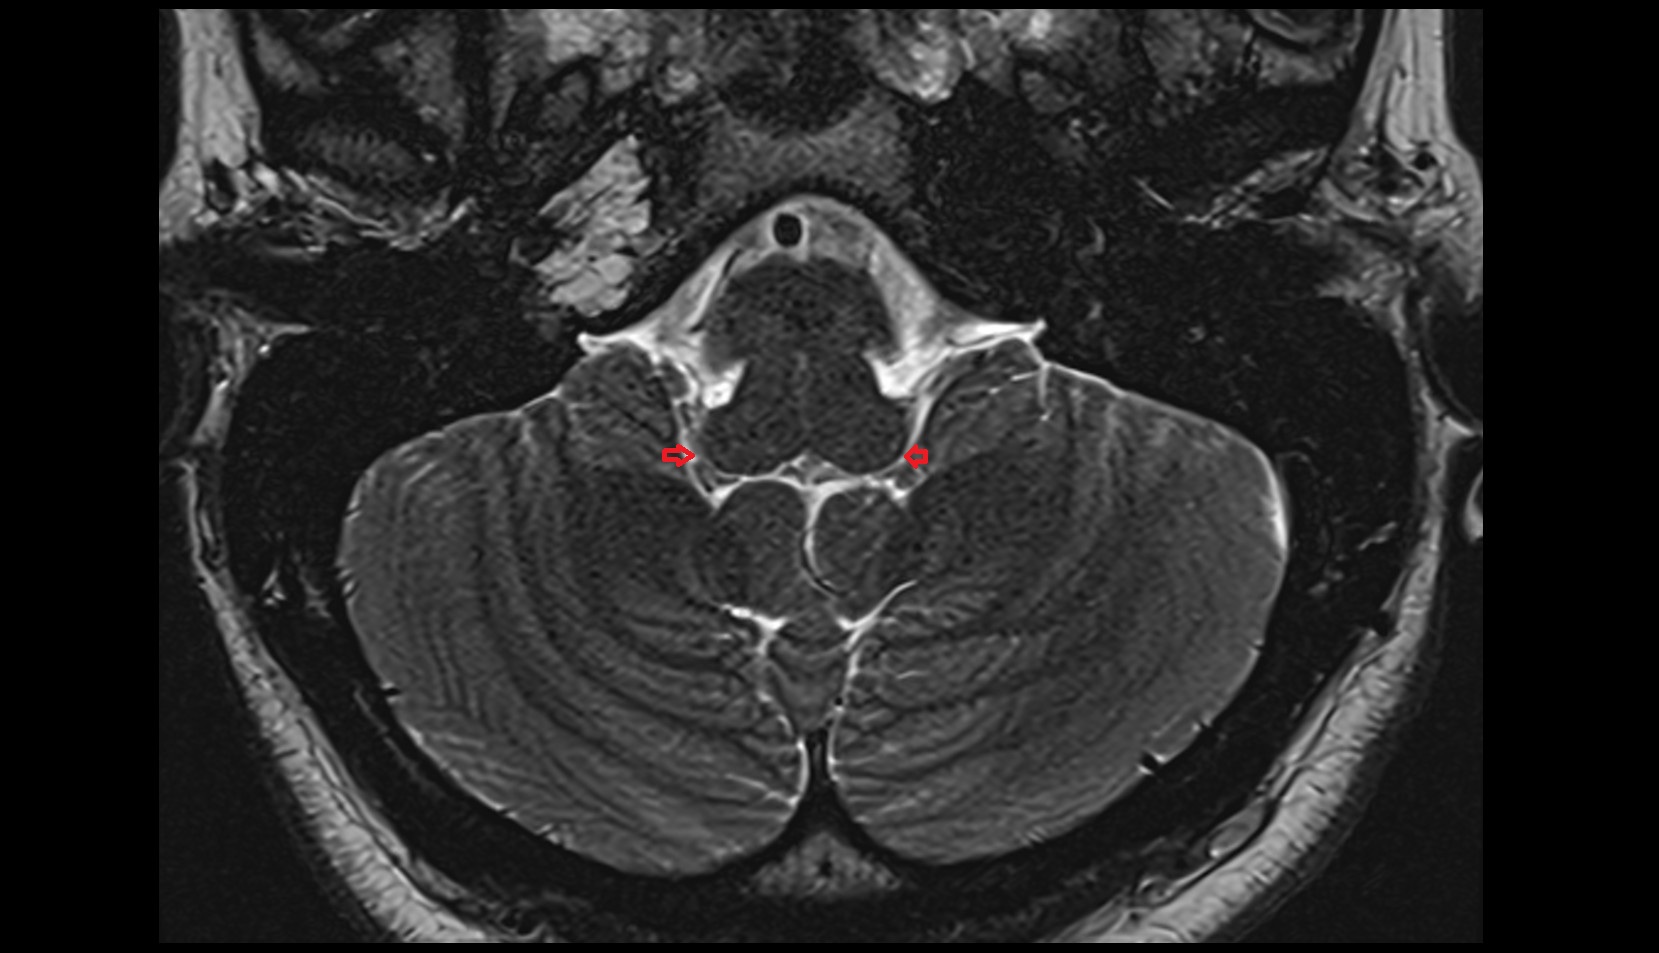

- Middle cerebellar peduncle

- Lateral aperture of fourth ventricle (foramen of Luschka)